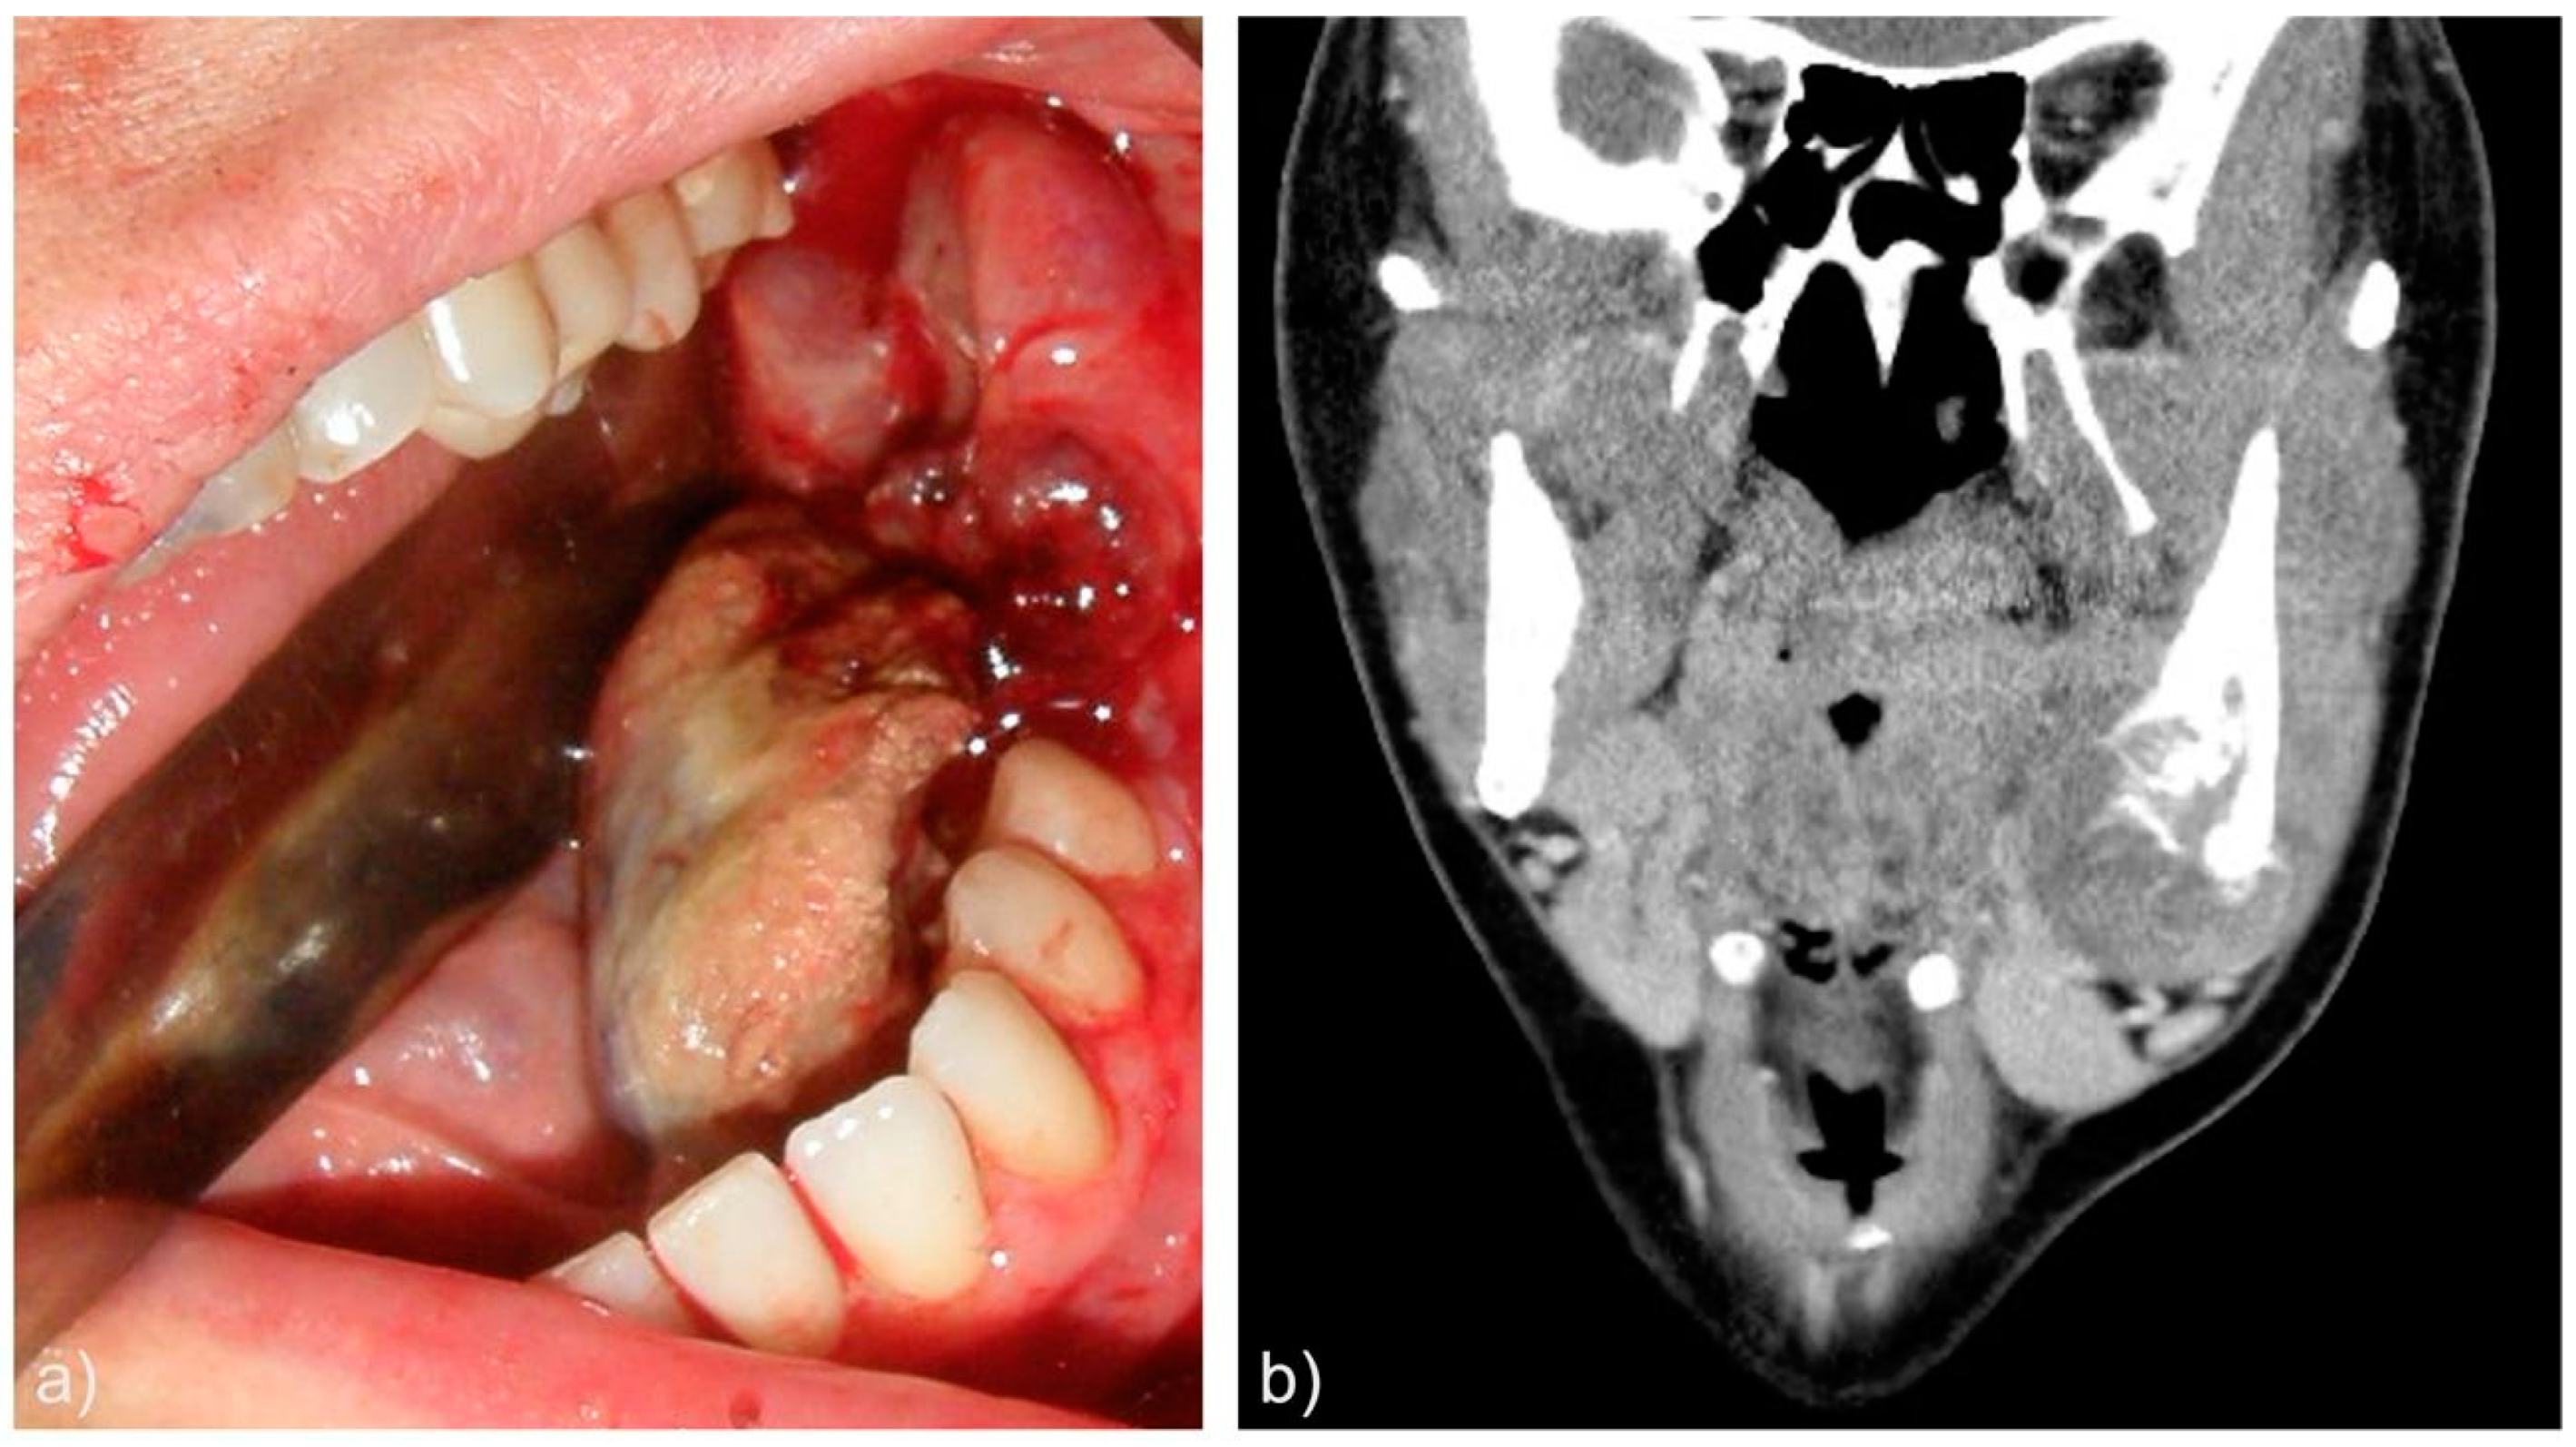

| 8 | 31 | F | Appendectomy at age 21 | Painful swelling Oral cavity bleeding |

Mandible (body and angle) | Left |

| Case | Histological morphology | Grade | Broders Classification | Soft tissue involvement | Lymphovascular invasion |

| 8 | Epithelioid | High | Grade 4 | No | Yes |